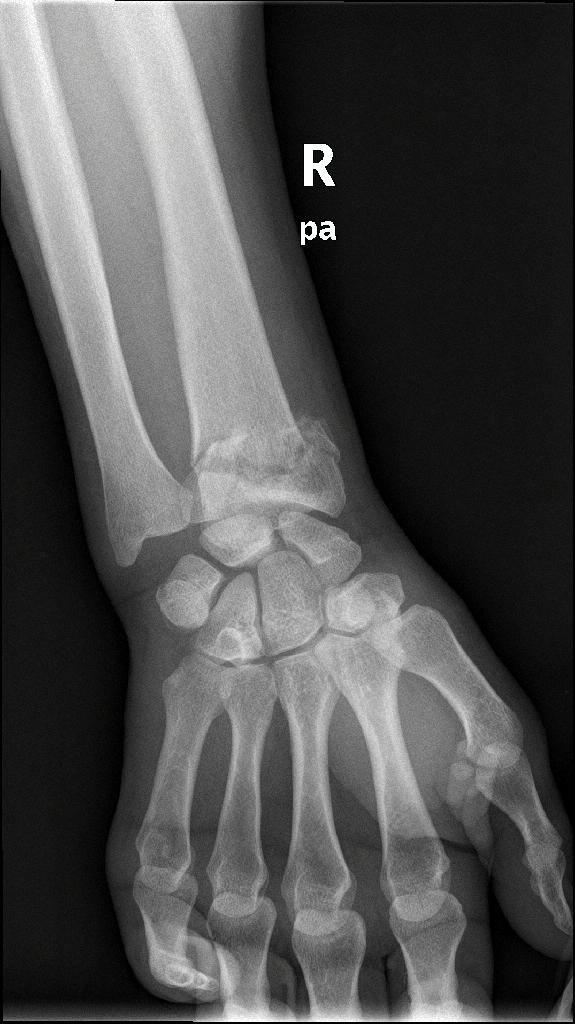

Περίπτωση 1ου ασθενούς